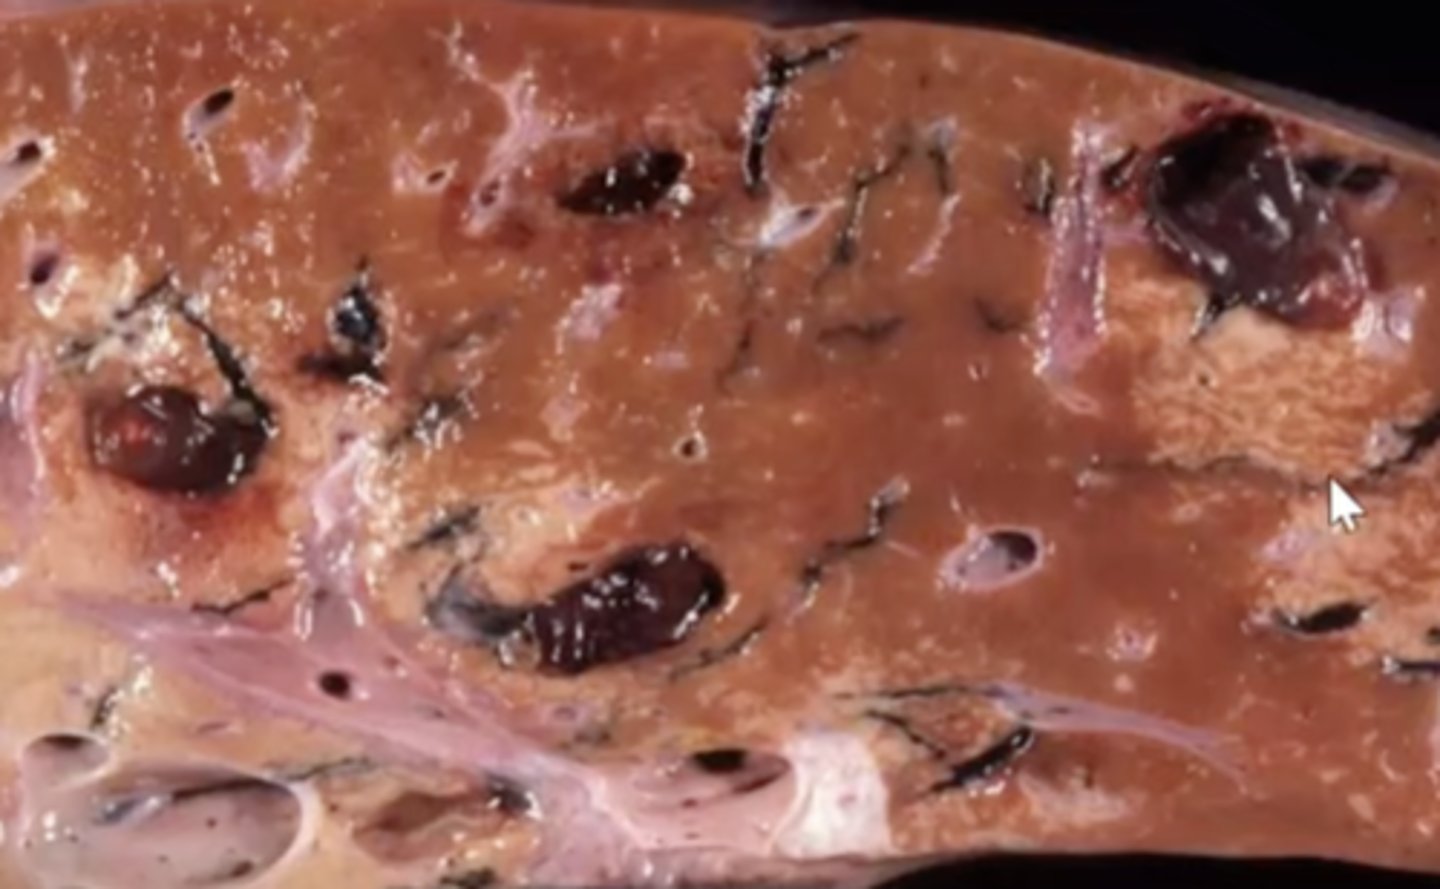

Fascioloides magna migration

-black lines

-hepatocytes have filled with fat (white spots) due to hypoxia

-fibrous connective tissue from damage

What has caused this gross appearance of this liver?